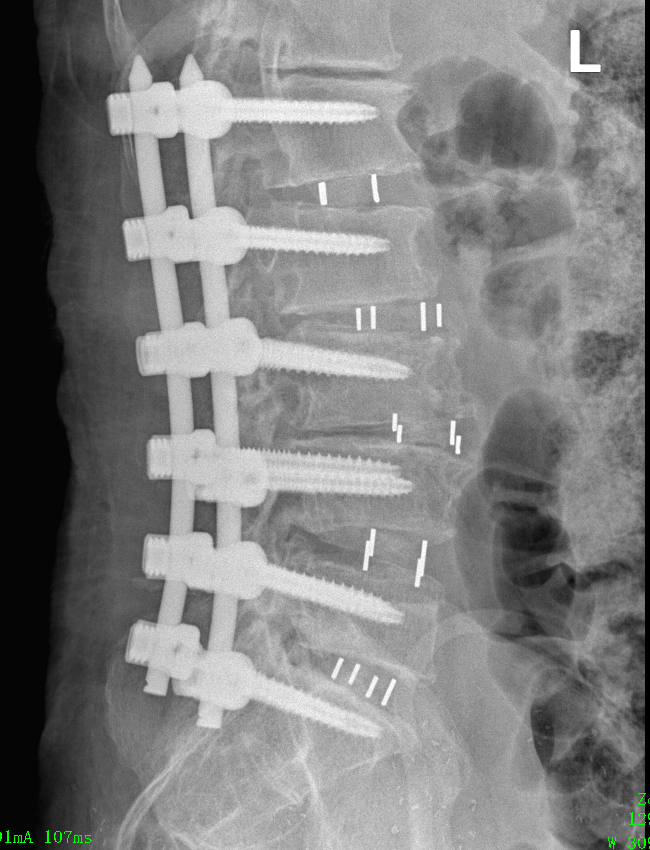

術(shù)后,患者經(jīng)過一周的休養(yǎng),身體狀況逐漸穩(wěn)定,隨即進(jìn)入第二階段手術(shù)。在腰背部,醫(yī)生采用經(jīng)皮微創(chuàng)技術(shù)置入12枚鈦合金椎弓根螺釘,進(jìn)一步矯正殘存的側(cè)彎畸形,且同時(shí)形成堅(jiān)強(qiáng)的內(nèi)固定,為脊柱的長期穩(wěn)定提供了有力保障。